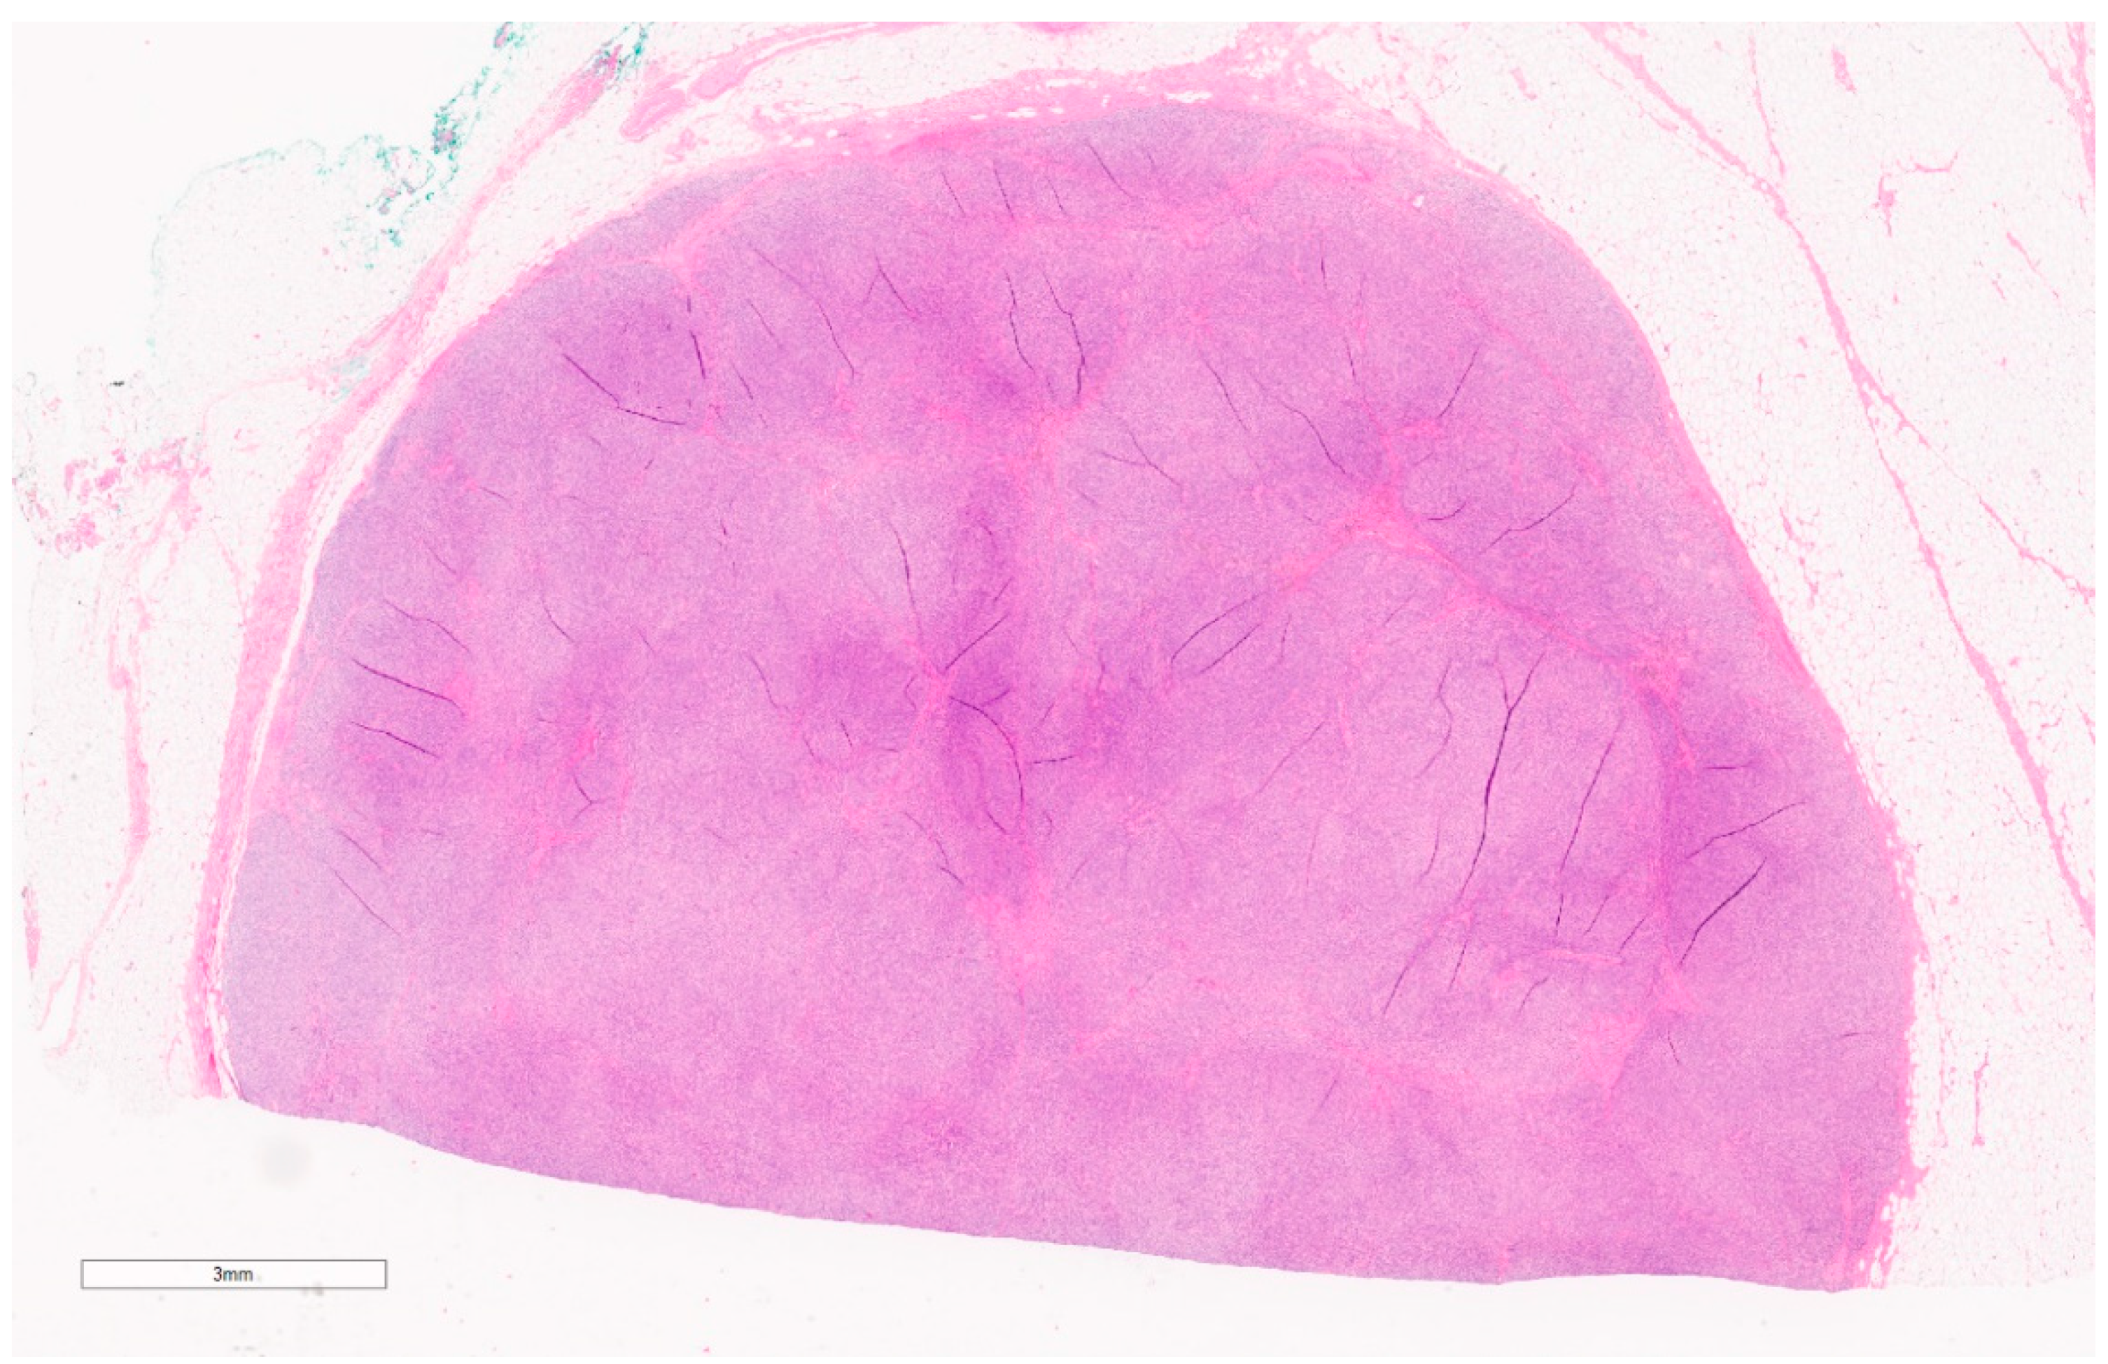

2.2. Myofibroblastoma

Summary of Updates